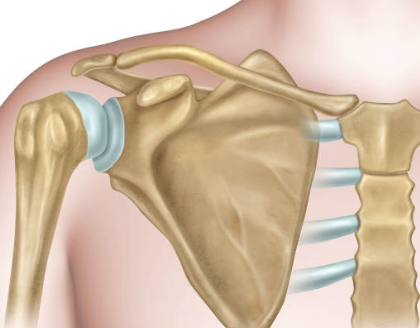

어깨 회전근개는 상완뼈와 견갑골 사이에 위치한 네 개의 근육과 그 근육들을 연결하는 건으로 이루어진 구조입니다. 이는 상체를 움직이는 데 있어서 중요한 역할을 합니다. 어깨 회전근개는 팔을 들거나, 회전하거나, 상체를 앞으로 내밀 때 근육을 동원하여 이를 가능하게 합니다. 어깨 회전근개는 근육과 건으로 이루어져 있기 때문에 손상이 발생하면 회복이 어렵습니다.